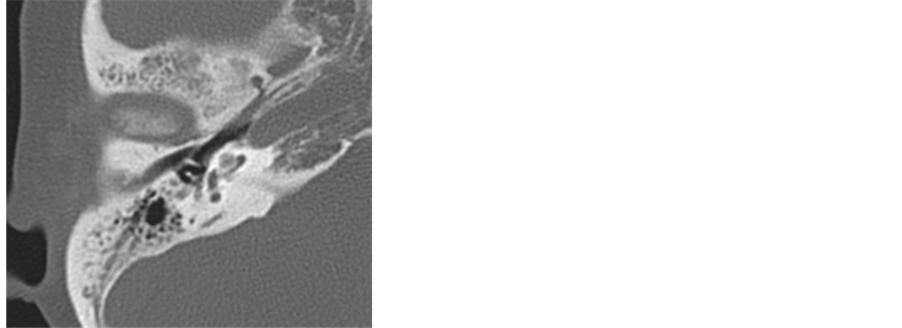

Case 1. A 53-year-old female was referred to our hospital for the investigation on progressive bilateral senso- rineural hearing loss. Thirty years previously, she had been diagnosed with bilateral chronic otitis media (COM). She was also diagnosed with chronic sinusitis without nasal polyposis, and she had been treated with steroid inhalation therapy for bronchial asthma. At the age of 49, bilateral profound sensorineural hearing loss was detected. On pathological examination, the middle ear mucosa contained numerous eosinophils and she was diagnosed with EOM according to the 2011 diagnostic criteria [6] . Pure tone audiometry showed bilateral profound hearing loss (Figure 1). Her speech recognition score was 10% (Japanese monosyllable list) in both ears. Temporal bone computed tomography (CT) and magnetic resonance imaging (MRI) showed no low density tissue in mastoid or tympanic cavities (Figure 2(a)). No ossification of the cochlea was evident (Figure 2(b)). As she did not present with any ear discharge, we recommend cochlear implantation. After systemic administration of a corticosteroid (dexamethazon 2 mg/day × 7 days), we performed cochlear implantation through the round window approach with miryngoplasty in her left ear. As no ossification of the cochlea was observed, flex electrode arrays (Med-EL Flex28) were used and inserted completely. No complications in relation to the implant device or skin flap were observed during a three-year follow-up. In spite of postoperative oral steroid administration, the tympanic membrane was re-perforated and ear discharge recurred at six months post-surgery (Figure 3). Even

Figure 2. (a) Preoperative CT of Case 1. No low density tissue in mastoid and tympanic cavity; (b) Preoperative 3D MRI of Case 1. Ossified cochlea was not evident.